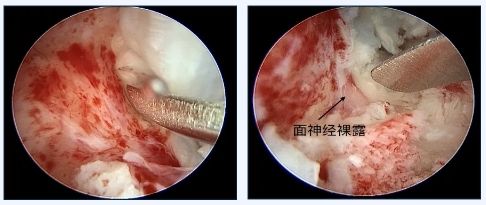

周彬主任带领耳科团队,决定采取最新引入的耳内镜持续灌流模式新技术,联合显微镜辅助进行手术。为了彻底清除中耳病灶,周彬主任先使用显微镜从乳突入路处理乳突和鼓窦病变,再用耳内镜从乳突进入越过面神经垂直段充分显露耳蜗底的巨大中耳脂胆脂瘤,在持续灌流模式下,持续高清的手术视野精准定位,逐步剥离胆脂瘤囊壁,直至彻底清除胆脂瘤病灶。手术过程中,发现白雪的面神经垂直段裸露严重,耳蜗底亦被纤维增生组织封闭,术后面瘫和眩晕是本次手术最容易出现的并发症,术前也对此种情况和家属做了重点沟通。